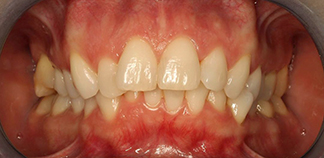

До лечения

Жалобы на не прорезавшийся зуб.

Как лечили

Проведено ортодонтическое лечение на брекетах. Верхний зубной ряд был сдвинут вправо для создания места под клык, зуб прорезался самостоятельно.

Лечащий врач

МАРЦИ Анастасия Викторовна